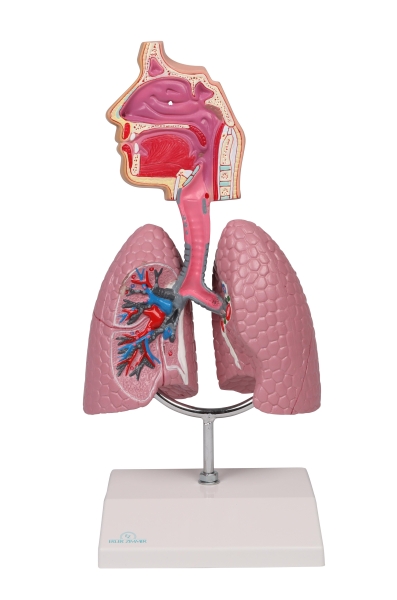

(G216) Human Respiratory System - EZ Augmented Anatomy

(G216) Human Respiratory System - EZ Augmented Anatomy

Representasi sistem pernapasan manusia berukuran sekitar setengah ukuran kehidupan. Paru-paru, trakea, dan saluran pernapasan bagian atas ditampilkan secara rinci. Model ini hadir dengan dudukan yang dapat dilepas.